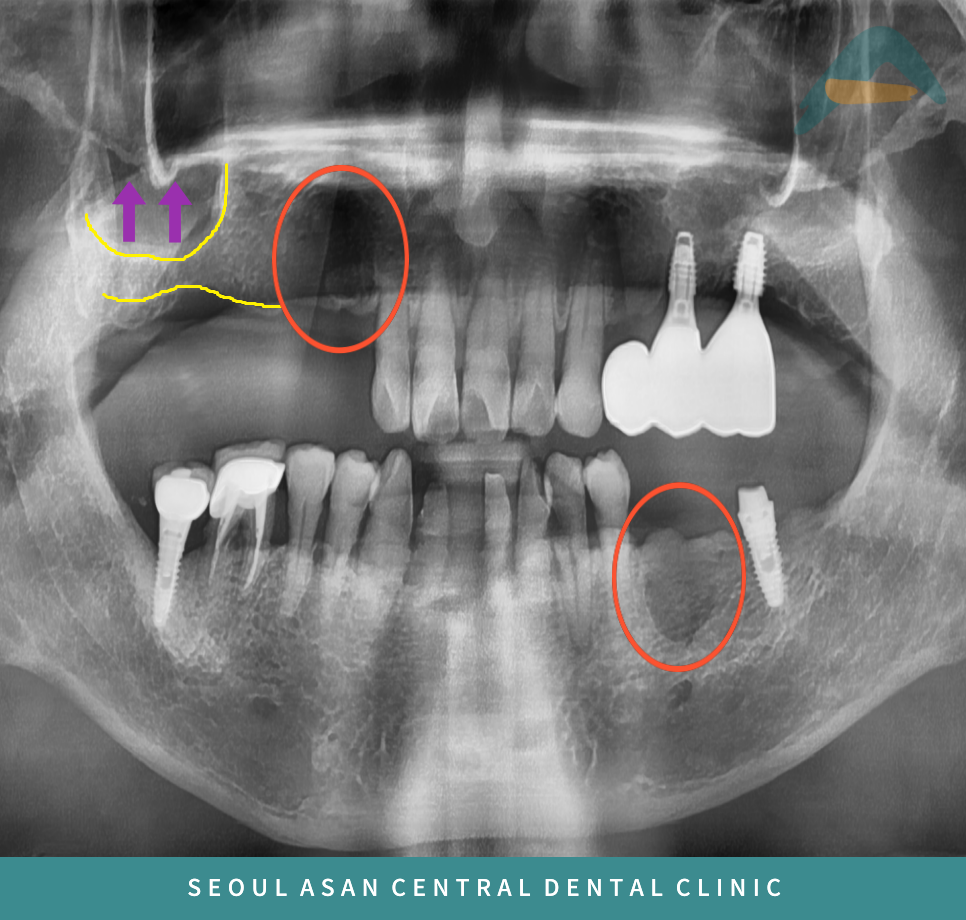

환자분께서는 위턱 오른쪽과

아래턱 왼쪽 잇몸뼈가 부족하여

임플란트가 어려워 성남치과

위턱 오른쪽 어금니 부위는

상악동이 내려와 있어

임플란트 식립을 위해서는

상악동 거상술이 필요하고

사진상에서 까맣게 보이는 것처럼

뼈가 많이 녹아 약해져 있다면

뼈이식을 동반하여

임플란트 식립이 필요할 수 있습니다.